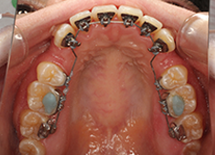

矯正歯科治療の中でも最もオーソドックスな治療法が、表側矯正(ワイヤー矯正)です。この表側矯正は歯にブラケットという装置を取り付け、そこにワイヤーを通して歯に力をかけながら、少しずつ歯を移動させて歯並びを整えていくという治療方法です。表側矯正(ワイヤー矯正)は最も適応範囲の広い治療方法です。

永久歯列の治療で、歯を動かすためにワイヤーの力を利用して歯の移動を行う装置をマルチブラケットアプライアンスと呼びます。

セルフライゲーションブラケット装置(デーモンクリア)、歯の裏側に装着するカスタムメイド型リンガルブラケット等の種類があります。ワイヤーを使わないものとして、マウスピース型矯正装置(インビザライン)があります。これは半透明なマウスピースを1日20時間以上装着することで歯を移動します。

リンガルブラケット